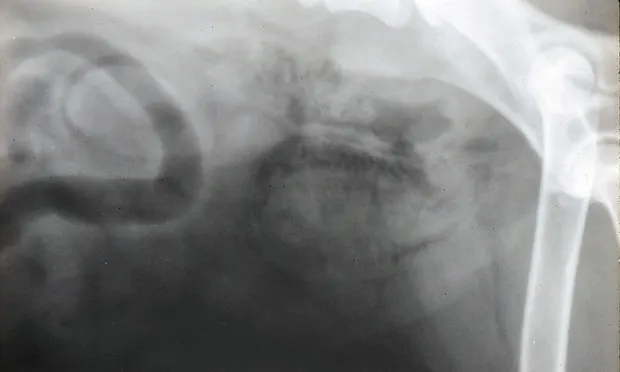

These radiographs are from different dogs with different underlying problems. The top figure shows mottling within the bladder wall of a diabetic dog that had not yet been treated with insulin. The mottling is caused by accumulated gas bubbles in the bladder wall. The bottom figure, which appears to be a pneumocystogram, is in fact a plain radiograph of an atonic bladder caused by a lumbosacral lesion that was interfering with bladder emptying. A secondary bacterial infection from urine stasis was causing the air accumulation that is shown. Management for both conditions requires urine culture and sensitivity, appropriate antimicrobial drugs, and treatment of the underlying disease.